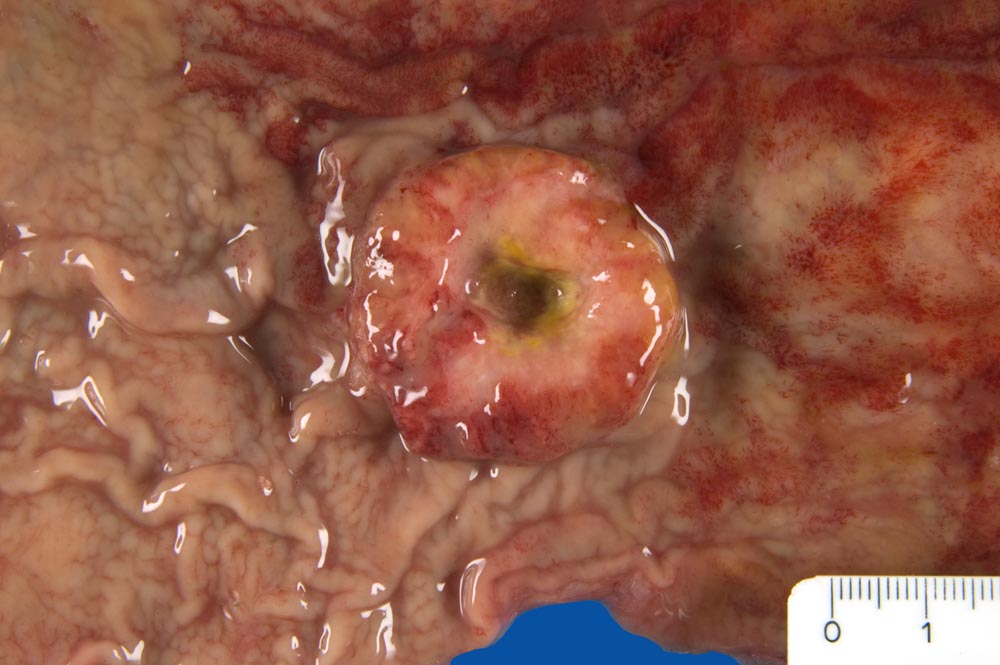

Ulzeriertes Adenokarzinom des Magenkorpus

Schüsselförmig exulzerierter Tumor des Magenkorpus.

Wenig differenziertes, invasives Adenokarzinom des Magens, intestinaler Typ). Metastasen in: Lungenoberlappen rechts (solitärer zentraler Rundherd) und Lungenunterlappen links, Pleura, Mediastinum, Schilddrüse, Nebennieren beidseits, Leber, Duodenum, Jejunum, Lymphknoten (paratracheal, infrakarinär, peripankreatisch und im Mesokolon), Milz, Brustwirbelsäule (Thorakal 5 und Thorakal 6). pT4 pN3 pM1.